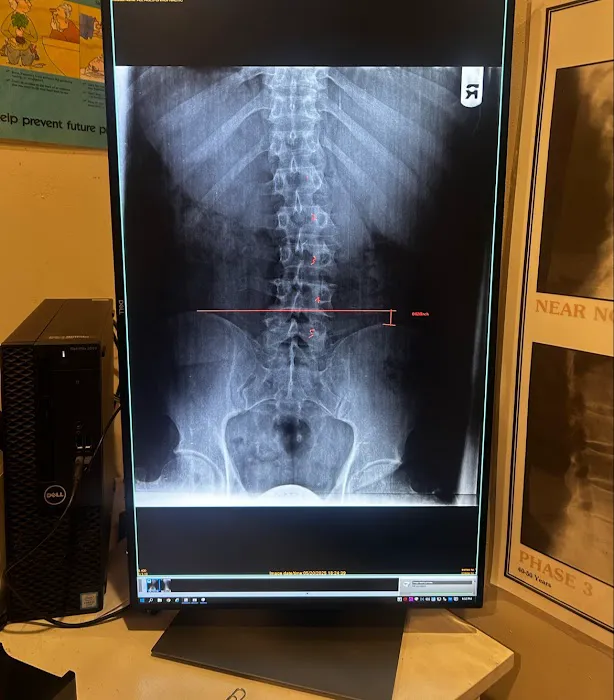

May 21, 2025 · Armando NoveloVery inviting and clean practice, staff is really friendly and informative. Never a long wait. What really got me was Dr Blum's ability to diagnose and treat my back problems. They took ex-rays and showed me how my spine and hips had become out of alignment and told me the process he would take to fix get me straight again.